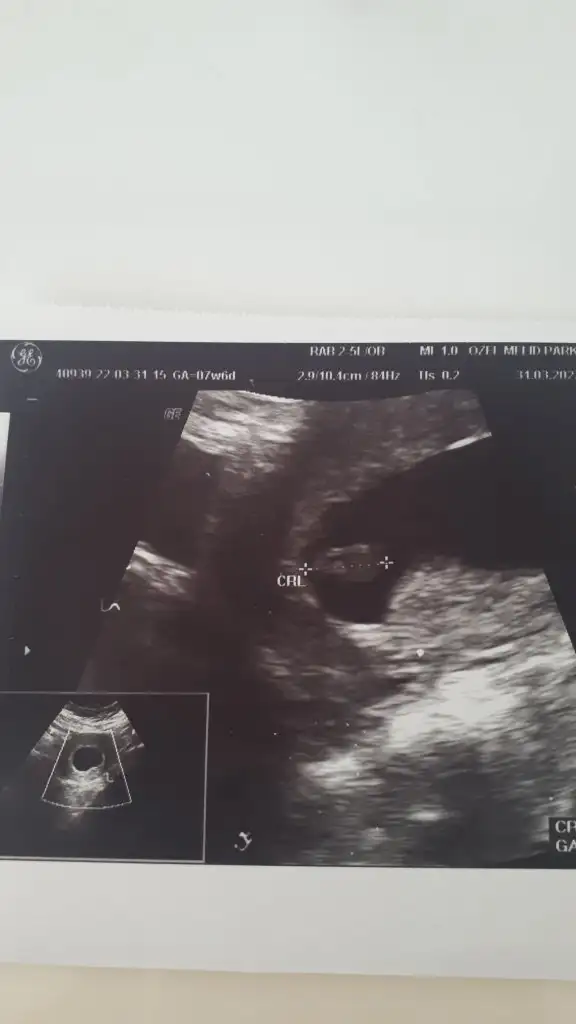

Pasha22 Pasha22 canım bir yakınım ultrason kağıdını atsam bakar mısın cinsiyete 7+4 günlük karından bakılmış 🤩